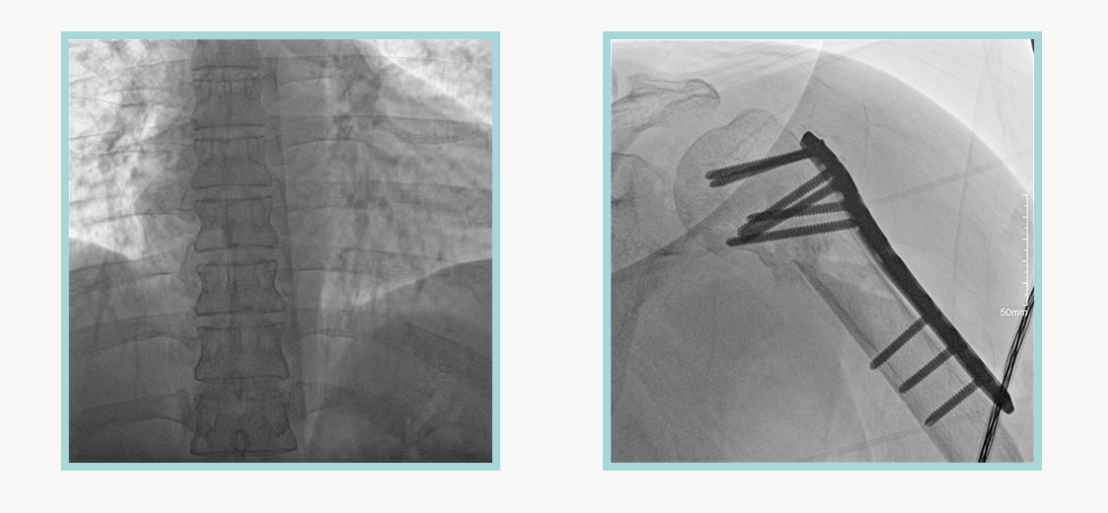

广东会科技悦画移动C臂X线摄影系统,采用了业内技术最尖端的CMOS探测器。基于性能优异的针状CSI闪烁体涂层和高灵敏度的CMOS感光芯片,悦画可以实现在超低X线剂量条件下实现高清晰影像成像,相较于一般的影增移动C臂和平板C臂,动态范围更高,影像的层次感和对比度更好。

在产品的性能参数设计上,悦画的像素可达到200万,空间分辨率可达到3.2线对,采用16bit的影像灰度,悦画在影像后处理上,通过SPI金字塔图像算法,支持摄影、脉冲透视影像、连续透视等多种模式下的影像采集,动态透视影像视频支持保存与回放。双大屏的设计,透视影像支持三档放大,保证临床影像读取的便利。

悦画在影像的伪影处理上,也积累多项图像处理专利技术。通过对植入物的精准识别,悦画能够精准祛除植入物伪影与运动伪影,保证高质量的影像输出,无论是影像的对比度、分辨率(清晰度)相较于市面上的移动C臂产品都更胜一筹。